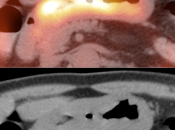

The difficulty with PET/CT imaging and gastric cancer is that it is both easy to overlook and easy to over-call.

Normal FDG uptake involving the stomach can be extremely variable. It is not uncommon to see diffuse intense uptake throughout the entire stomach or intense uptake limited to only a segment of the stomach (fundus, body or antrum).

In general, we raise a suspicion of gastric malignancy if:

• Focal or regional hypermetabolic activity is accompanied by at least the suggestion of associated wall thickening (often difficult to assess if the patient’s stomach is suboptimally distended with water or oral contrast);

• Uptake is extremely focal (more likely to represent malignancy or ulcer);

• Focal/segmental uptake is extremely intense.